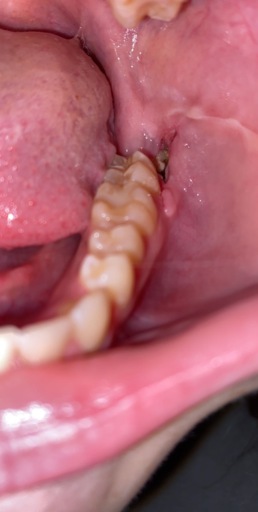

Hello. I have a small question. About 6 days ago, I had my wisdom teeth removed, and the dissolvable stitch between my right molars was super loose, and it came out with ease. And now the gum around my 2nd molar is very very slightly loose. Like when I pull down it's just a very little part where the gum can very slightly separate from the tooth (I mean VERY slightly). I don't think the stitch was doing anything with the fact I could rotate it with my tongue with very little effort. The gum didn't bleed, and it doesn't hurt, is this something to worry about? And how long will it take to heal?